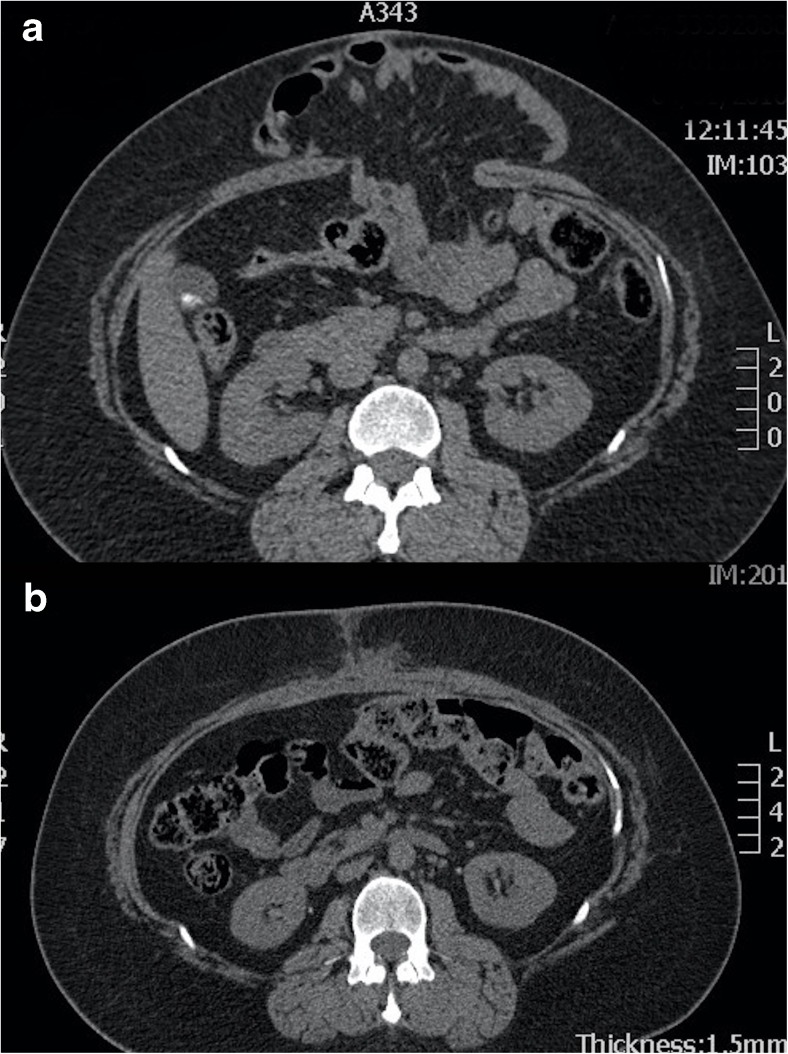

Preoperative CT will indicate the precise location of the hernia and provides prognostic information regarding the scale of subsequent surgery [20]; for example, smaller hernias may be closed using mesh alone (Fig. 5) whereas larger defects will need additional component separation (Fig. 6). Clinical examination by the surgeon will usually provide extensive information regarding precise anatomical site but imaging may provide unexpected information. Hernia extent on CT will also help indicate the scale of subsequent abdominal and cardiovascular insult (fluid loss is considerable during extensive CVH repair), so that appropriate preoperative conditioning, intraoperative support and postoperative care can be scheduled. Ultimately, by imaging the true extent of the hernia, CT is able to indicate which can be dealt with by “general” surgeons and which need attention from a CVH specialist.

Fig. 5.

a Preoperative axial CT showing a ventral hernia containing small bowel. b Postoperative axial CT showing ventral hernia repair achieved by apposition of the rectus muscles in the midline combined with an intraperitoneal mesh

Fig. 6.

a Preoperative axial CT showing a huge ventral hernia following sigmoid colectomy. b Postoperative axial CT showing ventral hernia repair achieved by bilateral anterior component separation combined with an intraperitoneal mesh